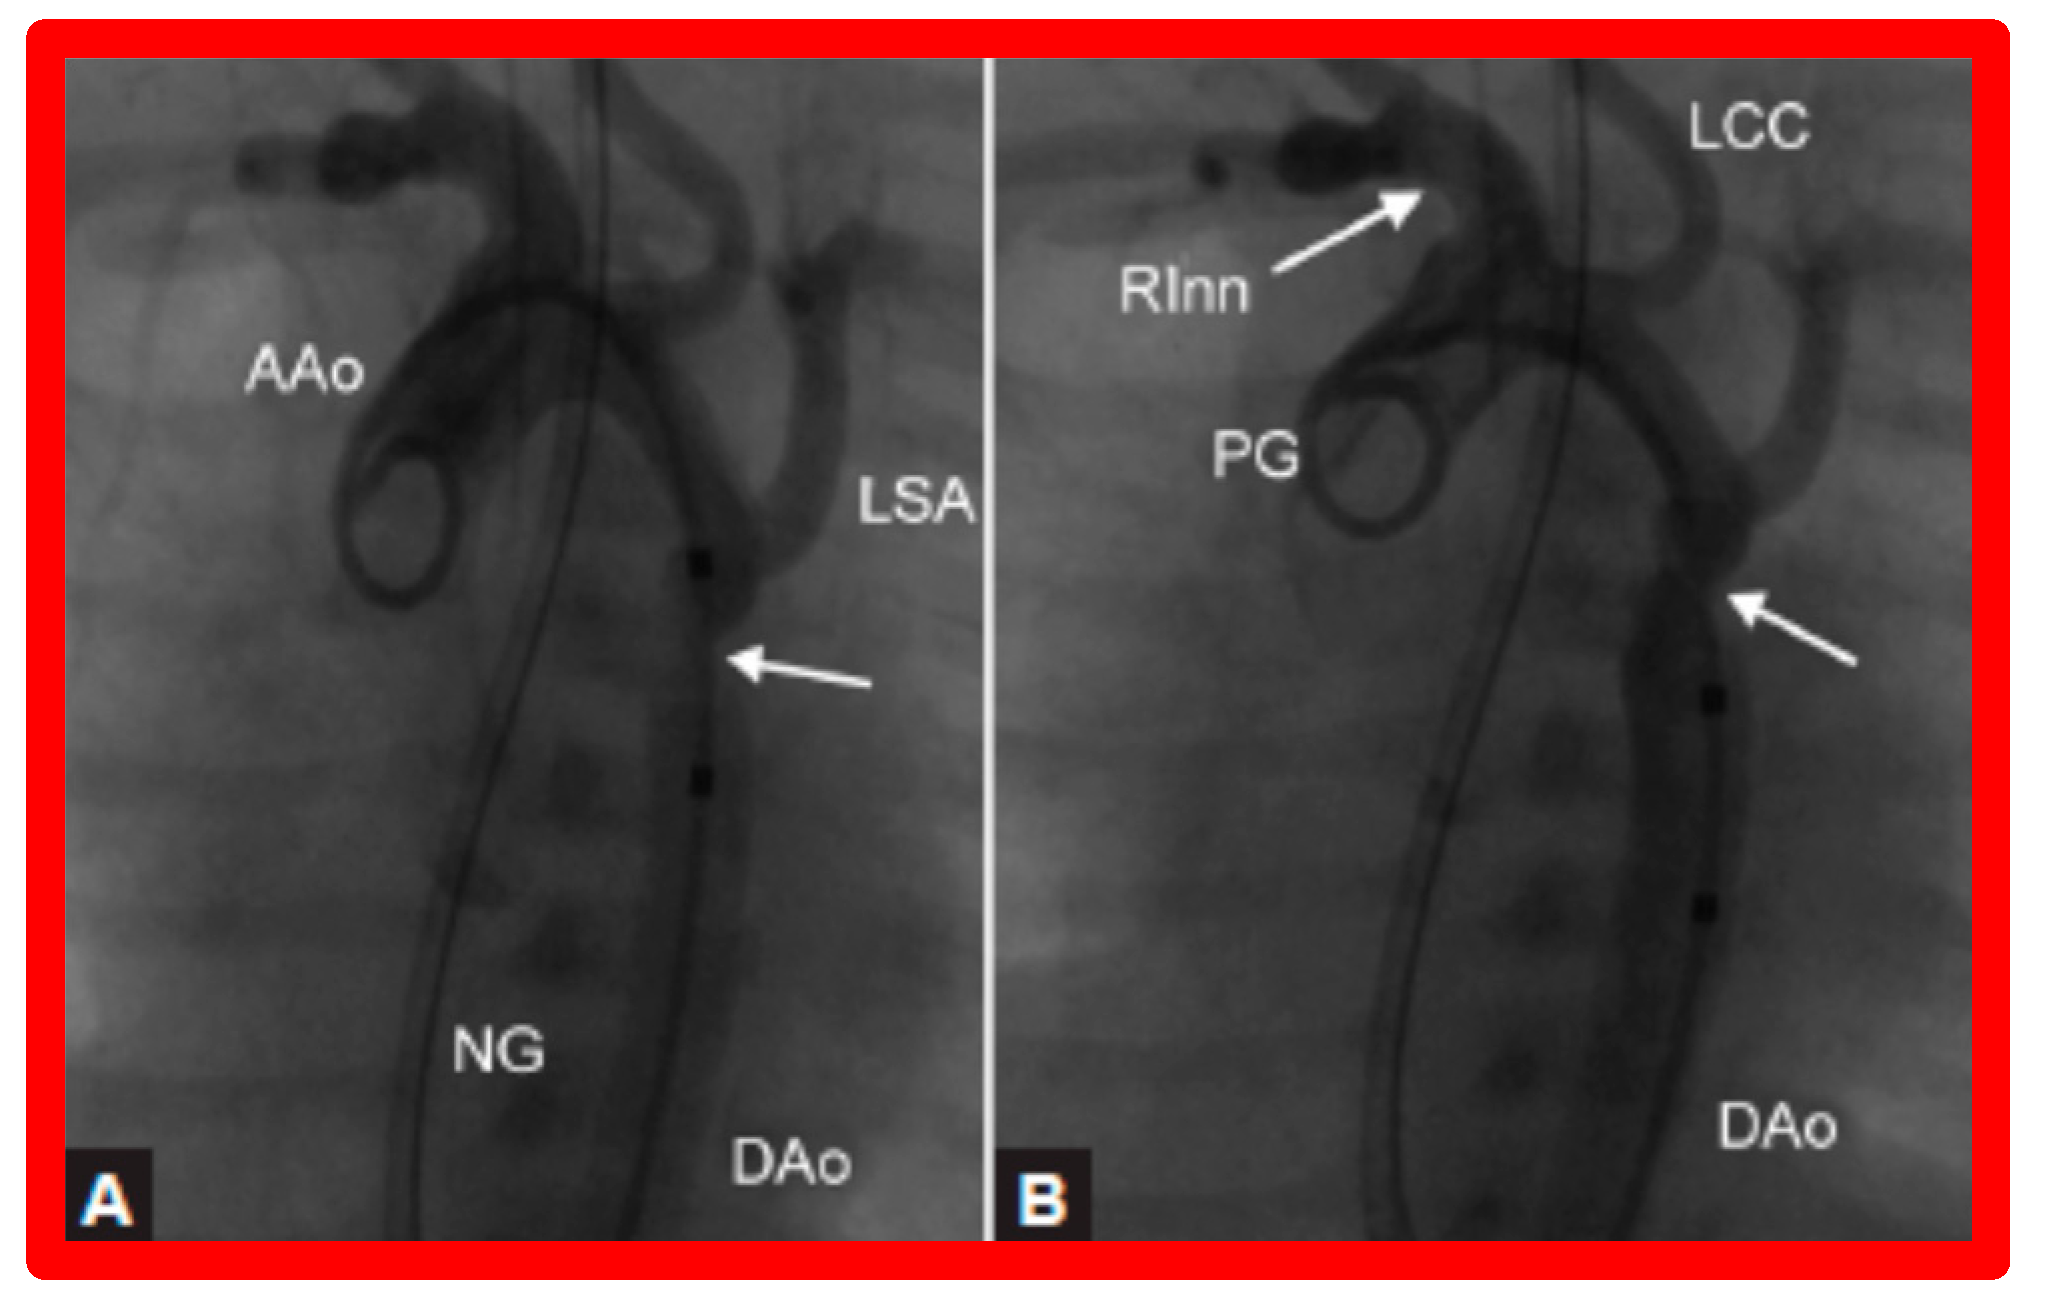

3.3. Aortic Coarctation, Native

4.3. Aortic Coarctation–Native

Revisit BA in the Neonate and Young Infant